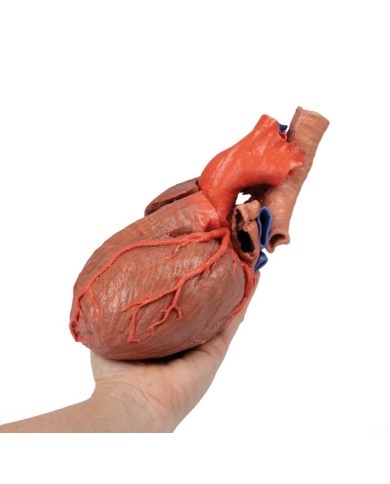

Modello di cuore di alta qualità scomponibile in 5 parti

Modello di cuore di alta qualità scomponibile in 5 parti

La parete anteriore del cuore è staccabile per poter vedere i ventricoli.

Realizzato in stampa 3D ad elevatissima risoluzione a colori.